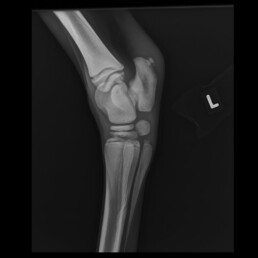

Nach vier Wochen wurden Kontrollaufnahmen der Gliedmaßen angefertigt. Hier ist im Vergleich zu den vorherigen Aufnahmen ein deutliches Voranschreiten der Ossifikation zu erkennen, jedoch ist die Ossifikation weiterhin unvollständig (Abb. 3 und Abb. 4). An der rechten Vordergliedmaße besteht zudem ein Carpus valgus mit einer Achsenabweichung von 10°.

Abb. 3 Tarsus links 90°: Hypoplastische Ossifikation Grad IV

Abb. 4 Carpus links 0°: Hypoplastische Ossifikation Grad IV